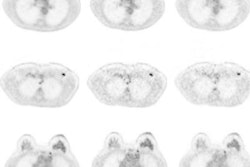

In their review of uncorrected and motion-corrected images, two radiologists found 162 PET-positive lesions in the liver, pancreas, kidney, bowel, rib, and shoulder among 32 patients. There were no detectable lesions among the other 10 subjects.

The radiologists achieved greater average sensitivity with the motion-corrected images (84%) than the uncorrected images (74%). In addition, the number of false-positive lesions decreased from 30 with the uncorrected images to 21 with motion correction. Peak standardized uptake values (SUVpeak) and maximum SUV (SUVmax) also increased with motion correction, as did the radiologists' confidence on a four-point scale.